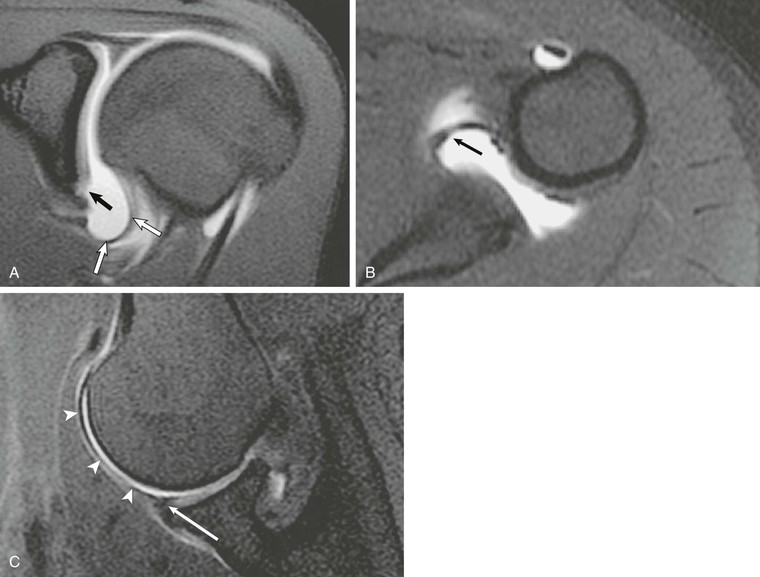

CT of the shoulder is performed primarily as a means of evaluating the osseous structures after trauma.12,13 Multidetector CT examinations with oblique sagittal and oblique coronal reconstructions can accurately detect the extent of humeral head and neck fractures. The precise number of fracture fragments, as well as the extent of displacement and angulation of fracture fragments, is accurately depicted. The scapula is a complex anatomic structure composed of the body, coracoid and acromion processes, and the glenohumeral articular surface. As a result, the full extent of scapular fractures is difficult to describe fully using conventional radiography, whereas the multiplanar capabilities of CT make it ideal for evaluation of complex scapular fractures. After glenohumeral dislocation, CT examination is the best modality to depict the size and position of a glenoid rim fracture fragment, which can be an important part of presurgical planning (Fig. 44-4). CT with three-dimensional reformations and subtraction of the humeral head is also the modality of choice for preoperative assessment of glenoid bone loss after anterior dislocations.14-16

Computed arthrotomography of the shoulder was widely used prior to the development of MRI and for years was considered the gold standard in the imaging of labral abnormalities.17-19 The combination of CT with intraarticular injection of contrast material provides a highly sensitive method of evaluating the glenoid labra and articular cartilage.20,21 During the past two decades, MRI and MRA largely replaced CTA in the evaluation of rotator cuff abnormalities and glenohumeral instability.22,23 Recent reports of CTA performed with use of multidetector CT (MDCT) demonstrated accuracy equivalent to or better than MRA for proximal biceps tendon,24 anterior labral injury, and superior labral anterior to posterior (SLAP) lesions.8,25 It is especially useful in the evaluation of the shoulder in a patient with a contraindication to MRI. Axial, oblique sagittal, and oblique coronal reformatted images are obtained to provide a better evaluation of the rotator cuff and labrum and to provide the same reconstruction planes as MRI (Fig. 44-5).

Although MDCT arthrography clearly depicts full-thickness rotator cuff abnormalities and many of the lesions associated with glenohumeral instability, MRI and MRA improve sensitivity in the detection of interstitial and bursal-sided tears, tendinopathy, and bone marrow edema without using ionizing radiation. Relative to CTA, MRI and MRA provide superior soft tissue contrast. However, MDCT arthrography with submillimeter-thick source slices allows exceptional spatial resolution, which assists in the detection of labral tears and the visualization of cartilage lesions.